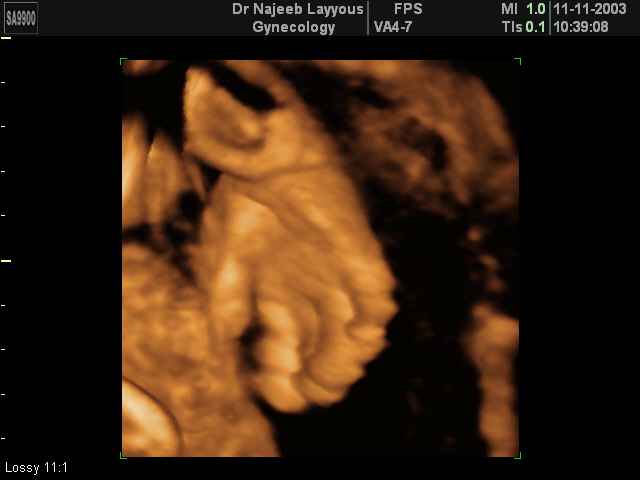

- صور لأعضاء الجنين

صور لأعضاء الجنين بجهاز الموجات فوق صوتية ثلاثي الأبعاد | الدكتور نجيب ليوس